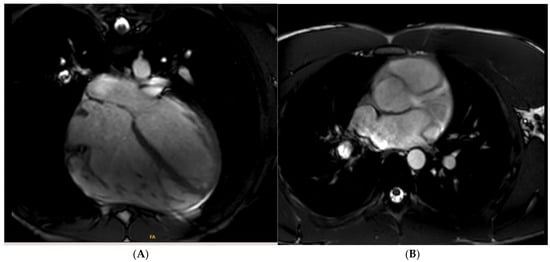

Tissue characterisation with cardiac MRI also plays a key role in athletes with a suspicion of HCM. Post-contrast imaging with late-gadolinium enhancement (LGE) is used to detect macroscopic replacement fibrosis (Figure 3). The presence of fibrosis is diagnostic of a disease process, often patchy and present in hypertrophied segments. Extensive LGE has also been associated with an increased risk of ventricular arrhythmias and SCD [67,68,69]. LGE is, however, only present in 60% of HCM cases [68,70], implying that the absence of fibrosis should not preclude labelling an athlete with HCM. T1 mapping has an important role in LGE-negative HCM cases. Myocyte hypertrophy, rather than expansion of the extracellular matrix, often leads to lower T1 values, especially in endurance and male athletes. This provides a valuable insight into the pathophysiological process of athletes with LV hypertrophy [71,72,73]. Pathological LVH, on the other hand, is positively correlated with ECV, suggesting that an increase in the extracellular matrix is the main contributing factor towards an elevated LV mass [74]. T1 mapping certainly holds promise, yet it requires extensive validation in large athletic cohorts with HCM. LGE and mapping sequences may also play a diagnostic role in HCM phenocopies when cardiomyopathy coincides with extracardiac manifestations. There is a typical abnormal post-contrast myocardial nulling in cardiac amyloidosis. T1 values are, conversely, significantly reduced in Fabry’s disease [75].

Figure 3. Caucasian male soccer player presenting with inferolateral T-wave inversion on ECG. SSFP cine imaging (A) showing apical hypertrophy, with evidence of apical fibrosis on post-contrast imaging (B,C).

Small-vessel disease and microvascular dysfunction is a phenotypic trait in some HCM patients, often leading to a demand and supply perfusion mismatch in HCM patients (Figure 4) [58,76]. One small study also confirmed that coronary vasodilation reserve is preserved in athletes with physiological LV hypertrophy but reduced in patients with HCM [77], suggesting it may play a role when evaluating athletes in the grey zone. Data supporting routine ischaemia testing in athletes with HCM are inexistent. For HCM athletes who report chest pain without a documented LVOT obstruction (either at rest or during exercise) and epicardial coronary disease, our current practice is to perform perfusion imaging to specifically rule out microvascular dysfunction.

Figure 4. A 21 year old male that presented with chest pain during a pre-participation evaluation to join the armed forces. ECG showing biphasic ST segments in leads V1-V3, with T-wave inversion in II/III/aVF. CT coronary angiogram ruled out epicardial coronary disease. A stress echocardiogram ruled out dynamic LVOT obstruction. Echocardiogram confirmed the presence of hypertrophic cardiomyopathy, secondary to a likely pathogenic MYBPC3 variant. Cardiac MRI (3T scanner) showing septal hypertrophy (arrow) (A), extensive replacement (arrow) (B), and interstitial fibrosis in the septal segments (arrow) (C) (T1 map using a MOLLI 5b(3b)3b [3T]). Perfusion imaging (D) also identifying an extensive perfusion defect (arrow) in the hypertrophied segments, confirming microvascular dysfunction.